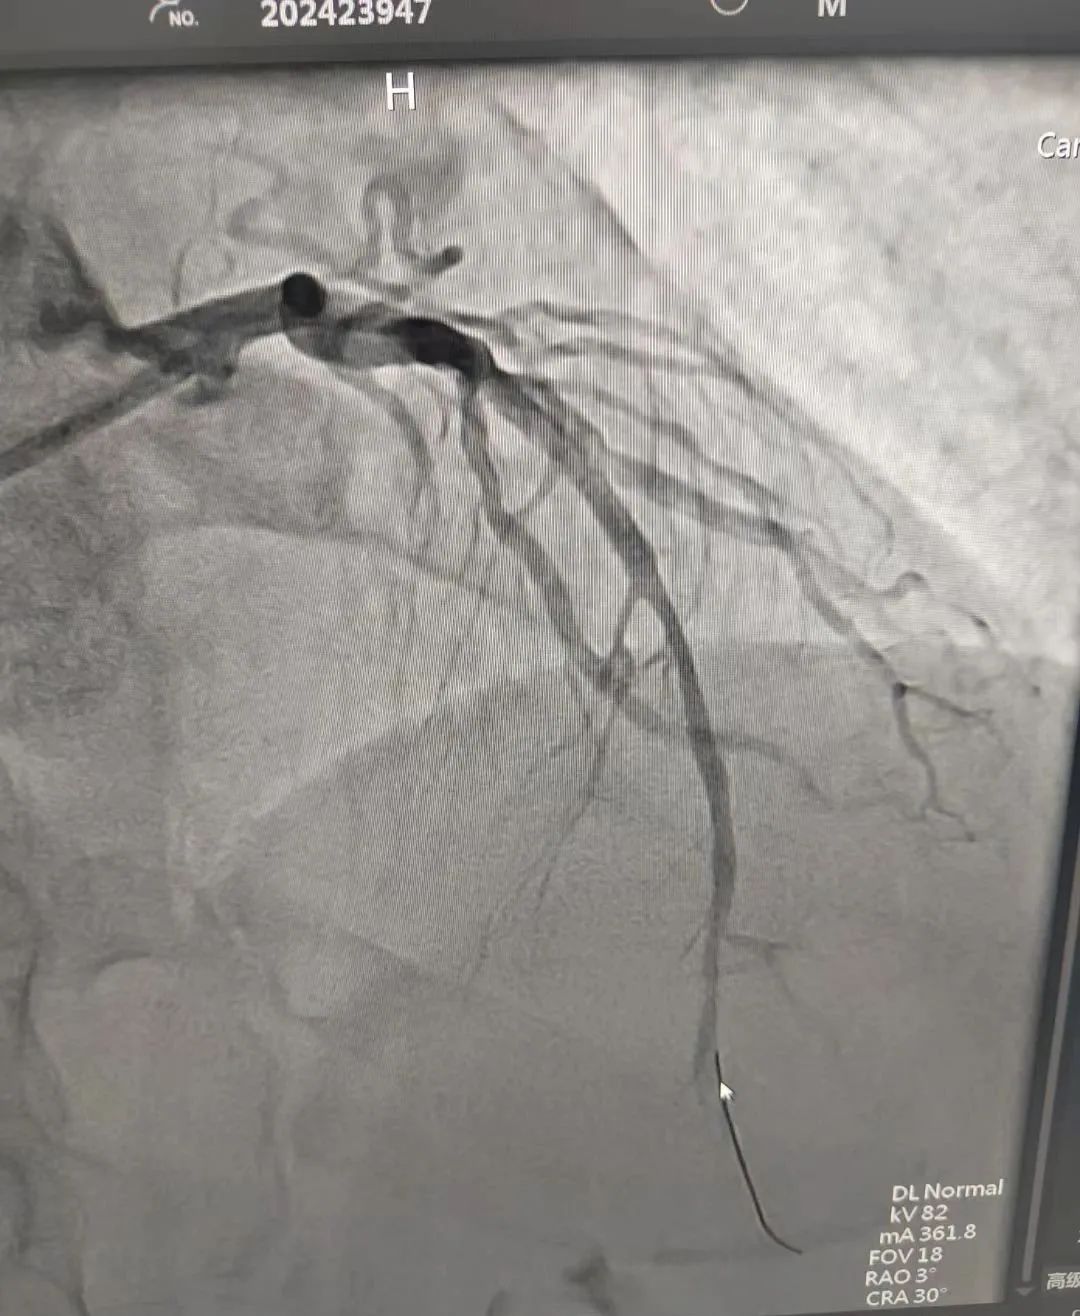

12月16日,患者黄某,因“胸痛14小时”到我院胸痛中心就诊,胸痛中心按胸痛患者救治流程给予绿色通道救治,心电图示;急性广泛前壁ST段抬高性心肌梗死,并与心内科密切配合,为患者及时救治提供高效保障。经造影检查显示:左前降支近段完全闭塞;第一对角支近中段弥漫性狭窄约50%~90%,回旋支远段弥漫性硬化狭窄约70%,右冠脉近段至远段弥漫性狭窄约50%~80%。立即给予前降支PCI治疗。患者已康复出院。